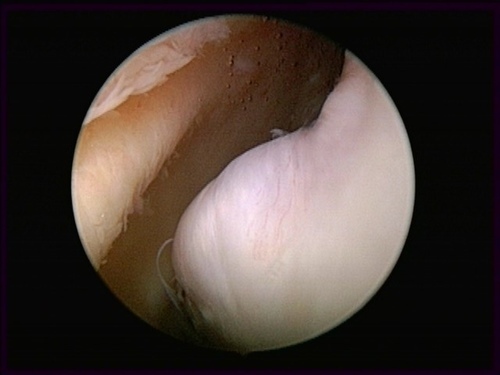

隱藏病灶                                                         手術清除中                                                      清除後